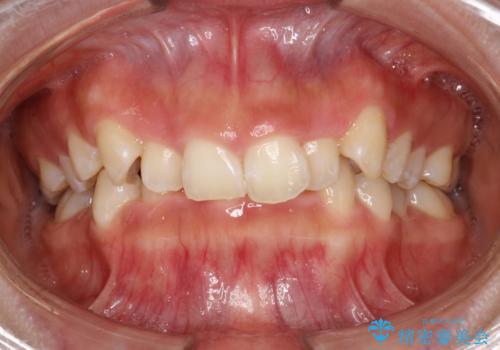

- 矯正治療前にステインを取りたいとのことで来院されました。ステインは前歯のみだったため、PMTC30分コースを行いました。

PMTCとは、歯科の専門家が器械を使用して行う歯のクリーニングのことです。普段の歯磨きでは取り切れない溝、キワなどの細かい部分も徹底的に除去します。ステインや歯石などが付着したままだと、虫歯や歯周病の発見がしずらいことがあります。特に矯正治療前には、念入りな虫歯や歯周病チェックが必要なため、PMTCでしっかりと汚れを除去しておくことが大切です。